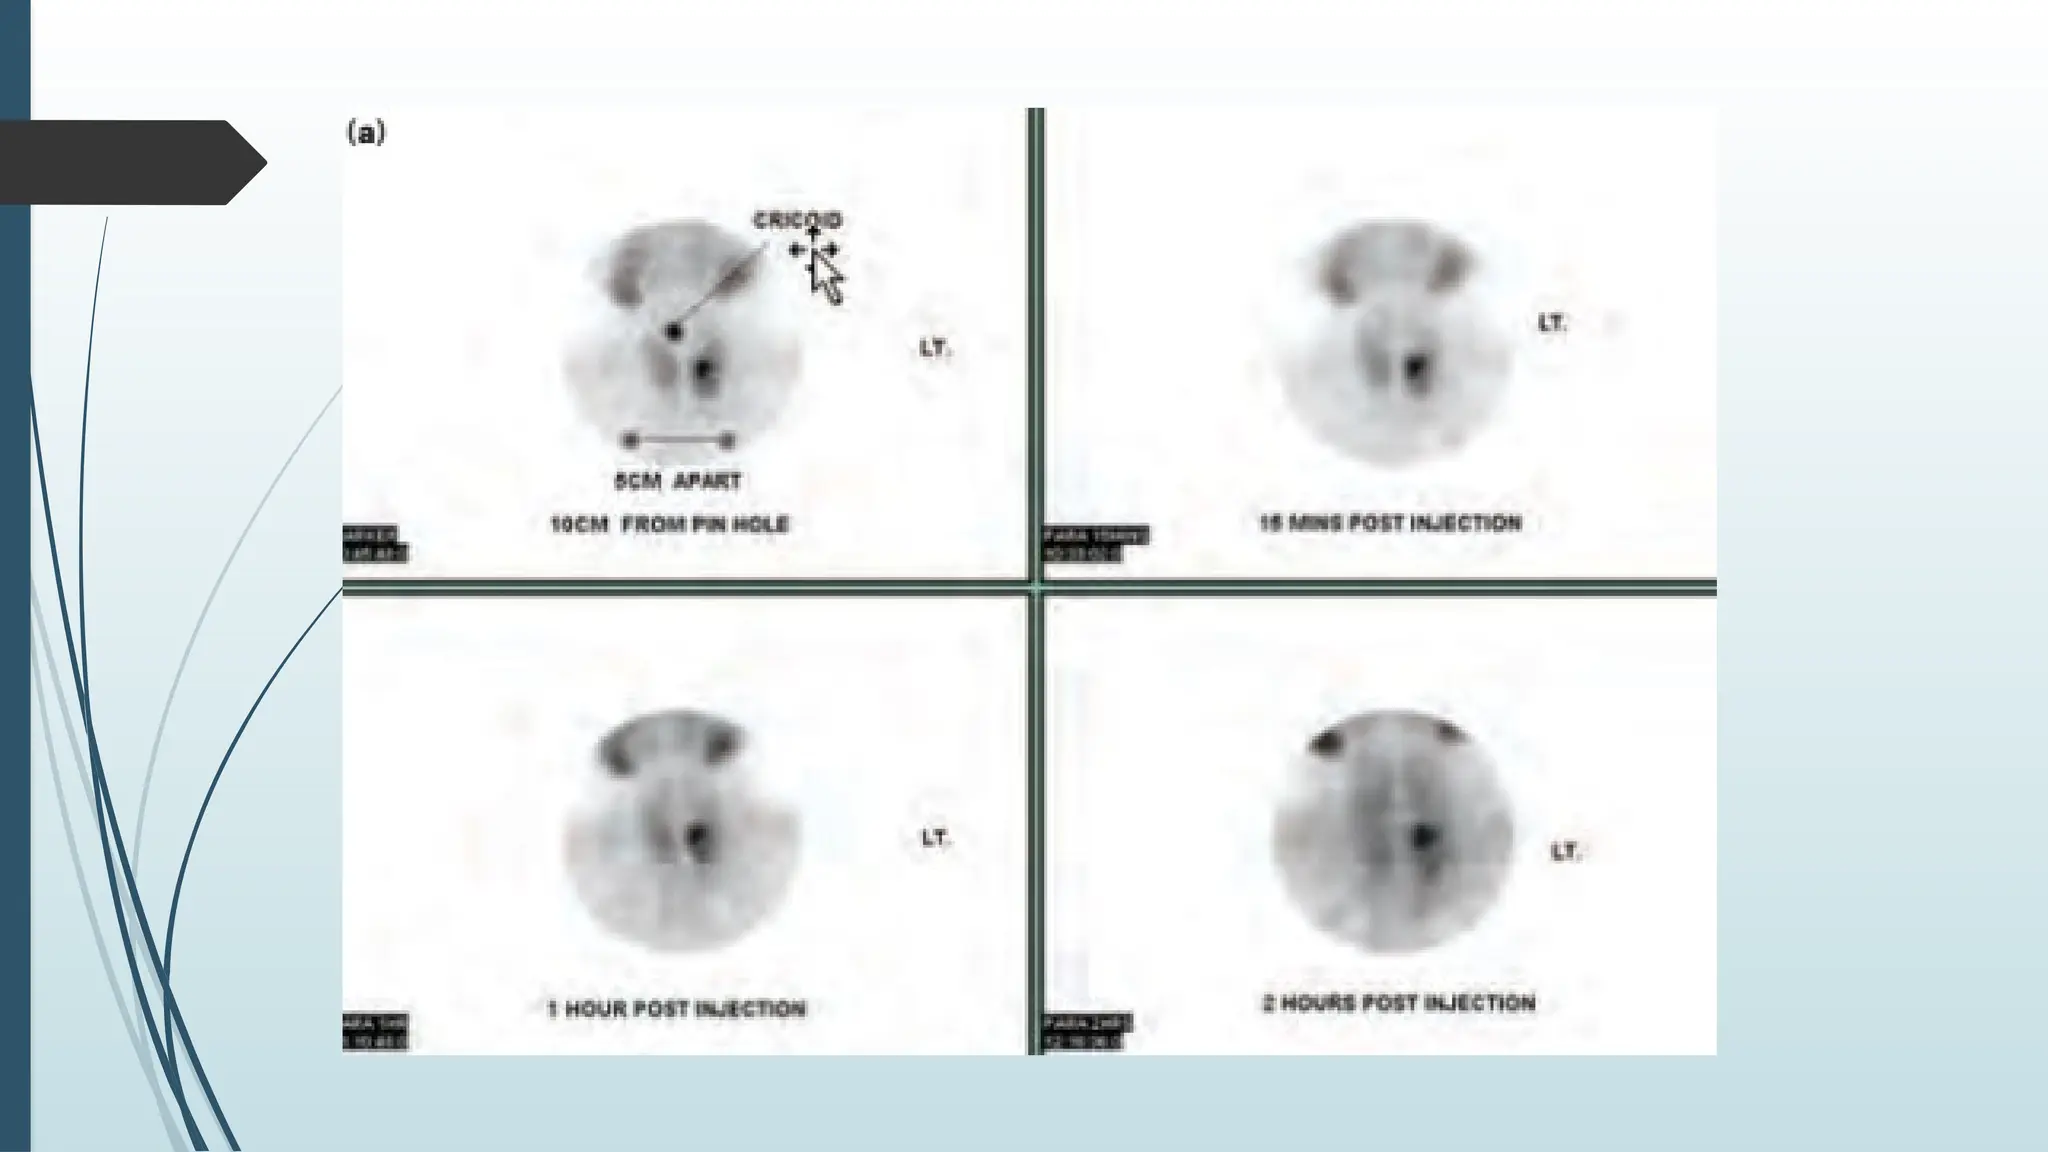

 Thallium-Technetium scan shows hot spots which is

diagnostic of parathyroid adenoma.

 Technetium-99m labelled Sestamibi isotope scan is better

and sensitive (80%)

 single photon emission computerized tomography (SPECT)

Investigations for HPT X-ray skull shows salt and pepper appearance and brown tumour  Ultrasound abdomen to find out problems in kidney, pancreas.  Ultrasound neck and CT/MRI scan neck and mediastinum.  Selective venous sampling for PTH is also very useful.  Thallium-Technetium scan shows hot spots which is diagnostic of parathyroid adenoma.  Technetium-99m labelled Sestamibi isotope scan is better and sensitive (80%)  single photon emission computerized tomography (SPECT)